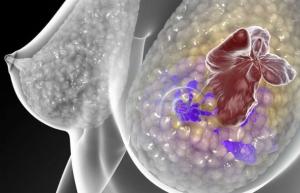

La densité mammaire est déjà documentée comme un facteur de risque de cancer du sein. Le tissu mammaire est sensible à l'exposition aux graisses au cours de l'adolescence, quand les seins se développent et subissent des changements structurels. Or certains facteurs liés à la morphologie du sein, tels que la densité, sont directement impliqués dans le risque de cancer du sein et même dans son dépistage. Une étude d'association pangénomique (GWAS), publiée dans BMC Medical Genetics conclut ainsi sur la relation entre la taille des seins et le risque de cancer. Elle identifie en effet 7 SNP ou variantes génétiques, associées à la taille des seins, dont 3 sont fortement corrélés avec le cancer du sein mais qui tous ont des liens étroits avec le cancer du sein, sur le plan hormonal par exemple. Une autre étude suggère qu'outre l'âge, les antécédents familiaux et l'âge des premières règles, deux autres facteurs sont associés à un risque plus élevé de développer un cancer du sein : la densité du sein par mammographie et l'étendue de l'involution lobulaire. C'est pourquoi les chercheurs du Maryland ont décidé d'étudier si l'apport en graisses pendant l'adolescence était associé à la densité du sein à l'âge adulte précoce.

Une différence de 5-6 points qui peut paraître modeste, cependant qui suggère bien un risque accru de cancer du sein. Des résultats qui vont dans le sens d'effets possibles à long terme de l'apport en graisses pendant l'adolescence sur la composition du sein adulte.